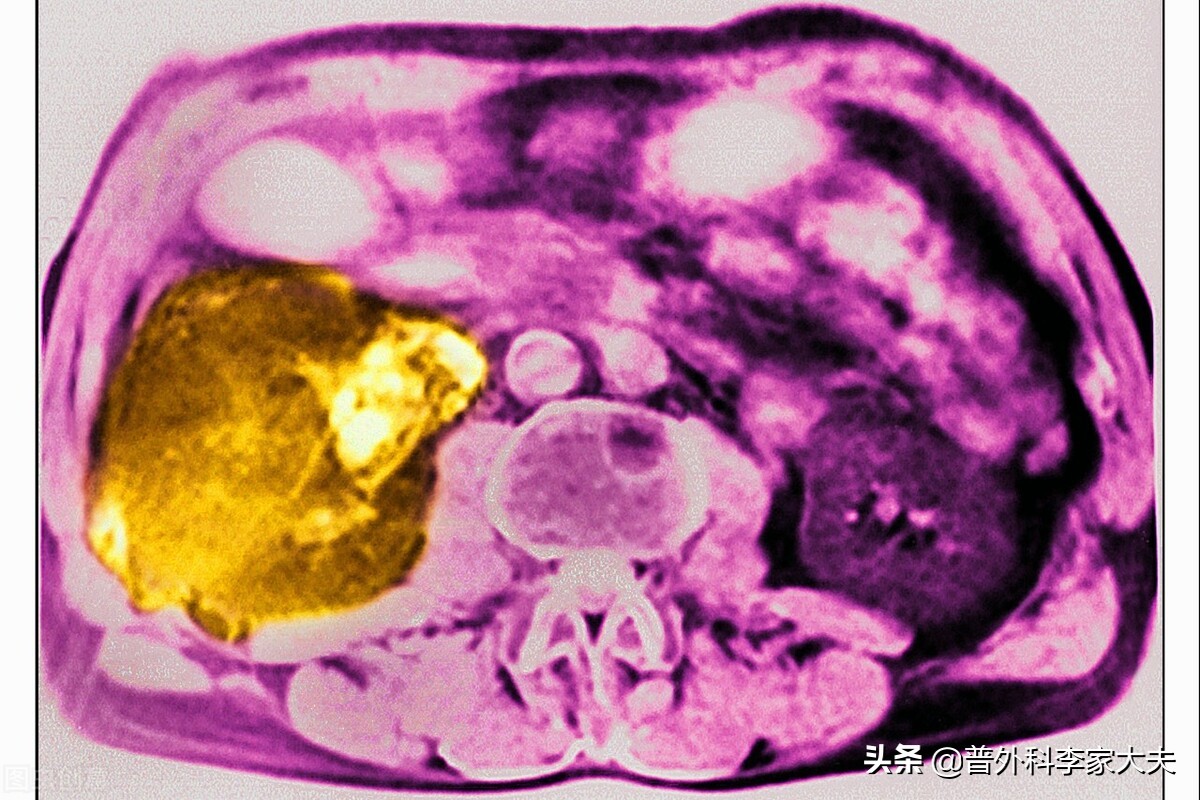

肝癌